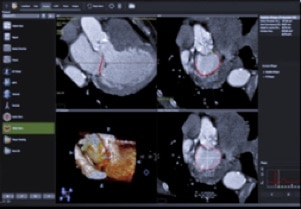

TAVI

- La soluzione Valve ASSIST 2 comprende TAVI Analysis, HeartVision 2 e richiede una workstation AW con Volume Viewer, Volume Viewer Innova. Queste applicazioni sono vendute separatamente.

- INTERACT ViewX è un kit di connessione per visualizzare le immagini interventistiche sul display del sistema ecografico GE. Richiede i sistemi Vivid E95 o Vivid S70N venduti separatamente. Si riferisce alle funzioni di Innova IGS 5, Innova IGS 6, Discovery IGS 7 e Discovery IGS 7 OR